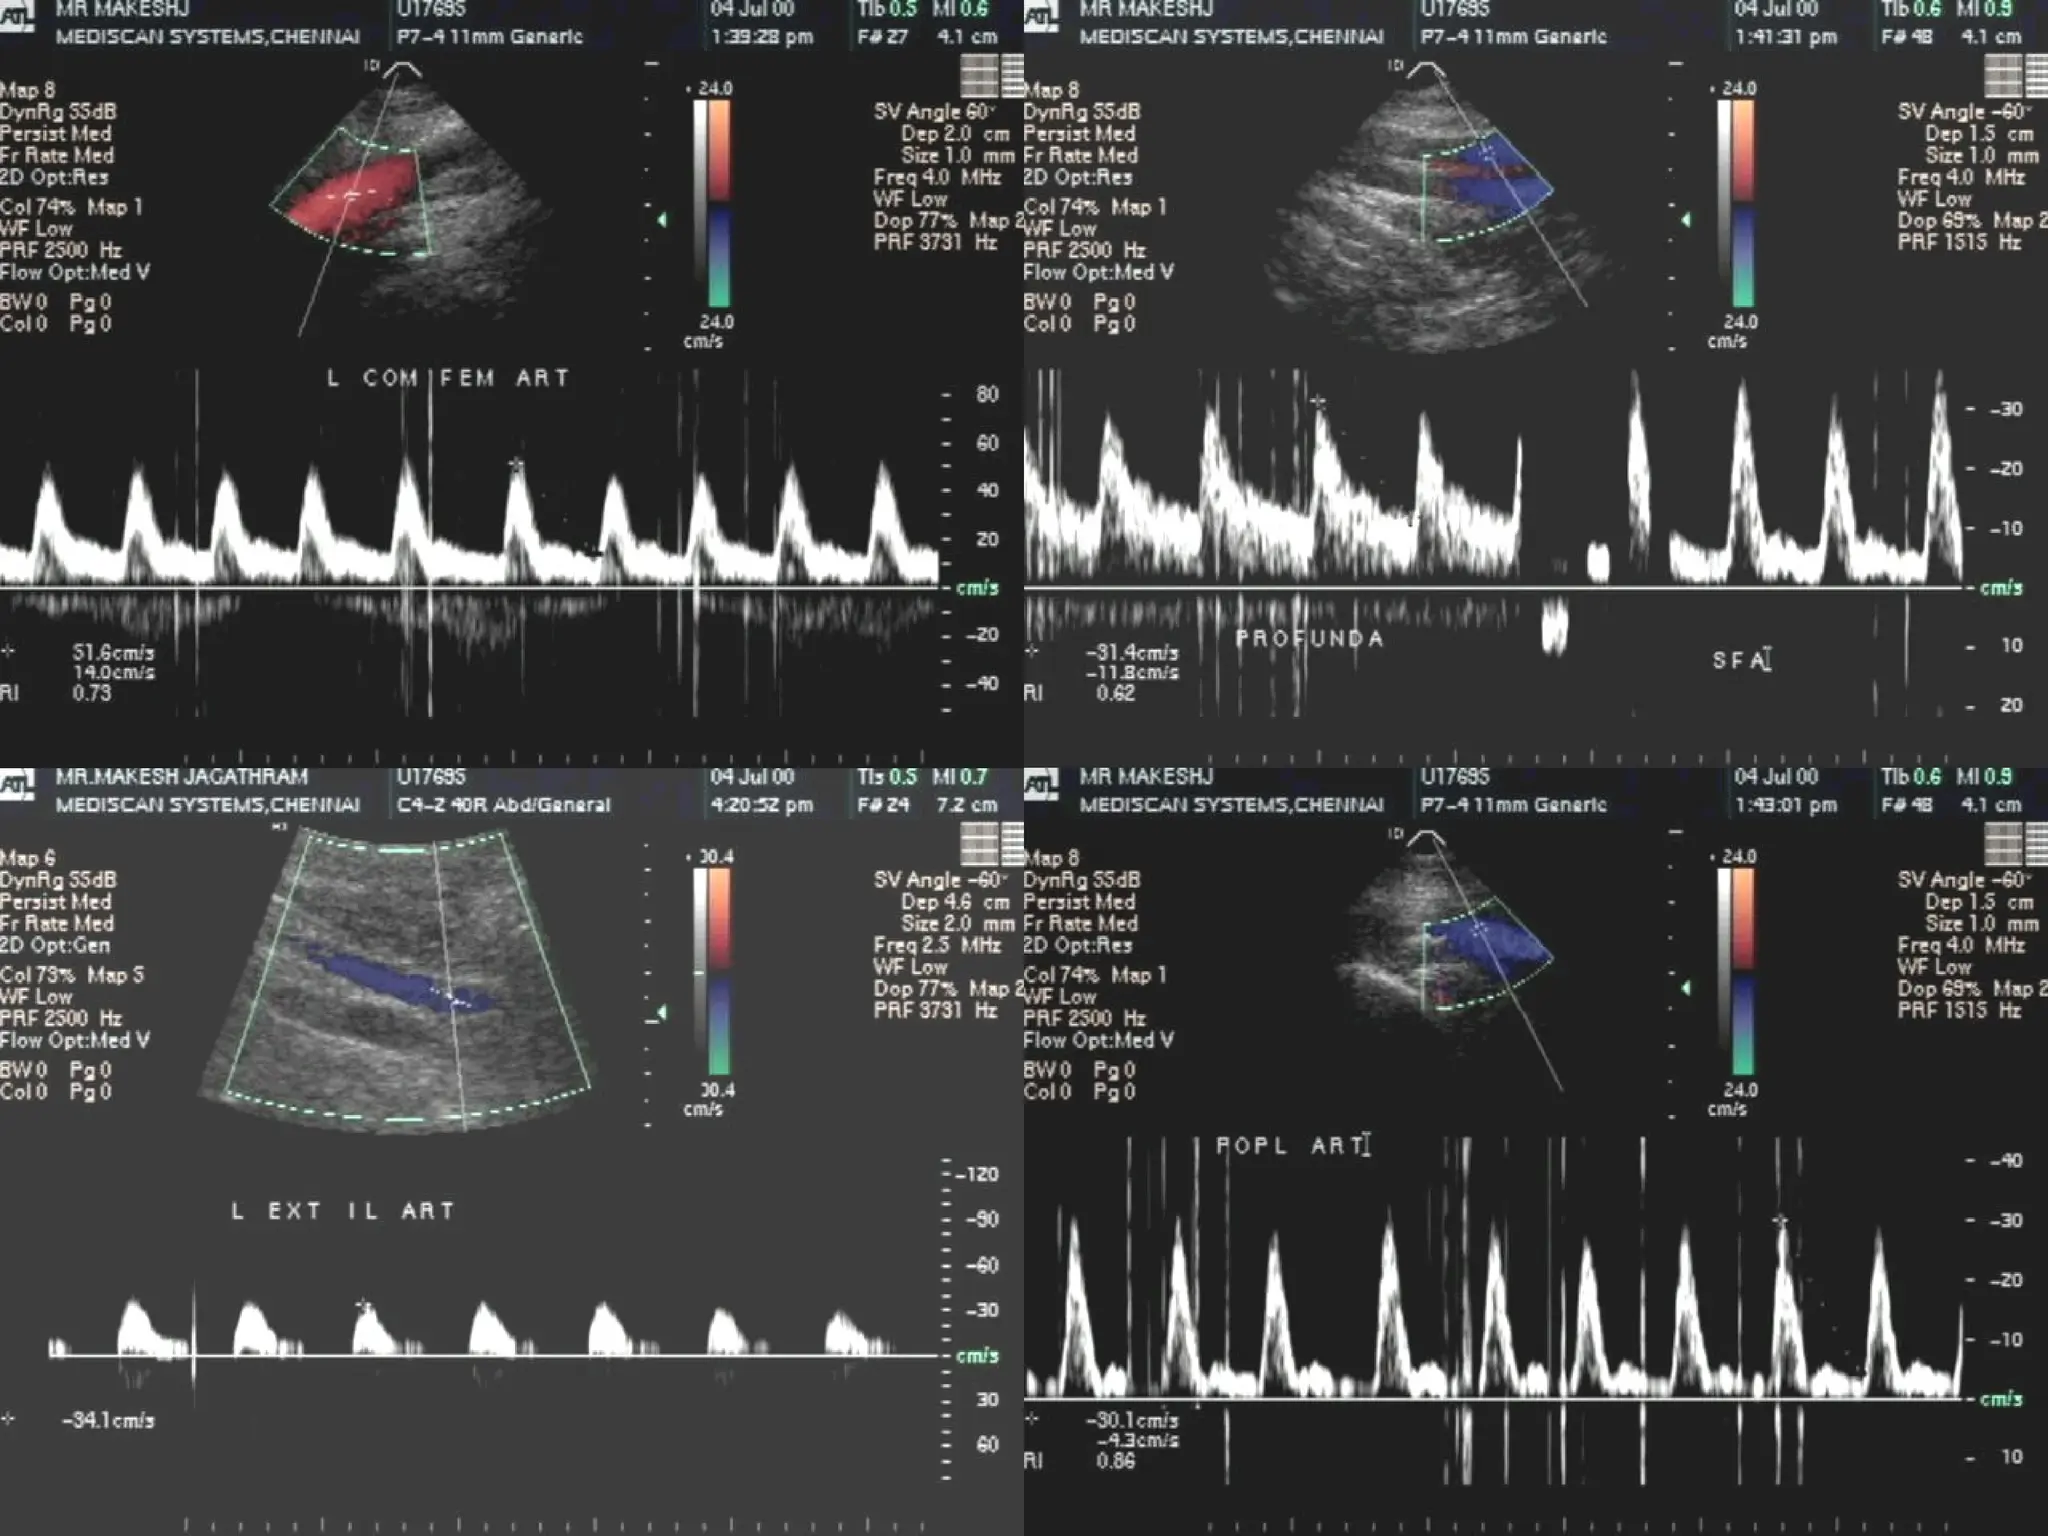

CASE I

 Mr. M, 35 yrs

Mr. M, 35 yrs

 Intermittent claudication – LLB,

Intermittent claudication – LLB,

1yr

 Smoker – 5 yrs

Smoker – 5 yrs

 Diabetes – 6 mths

Diabetes – 6 mths

Segmental pressures

AAI – 1.0 AAI – 0.75

Post exercise

Patient had unbearable pain in left leg after 3mnts.

USG FINDINGS

 Total occlusion of left common iliac artery.

Total occlusion of left common iliac artery.

 Left external iliac artery was fed by the left

Left external iliac artery was fed by the left

internal iliac artery.

 OCCLUSIVE ARTERIAL DISEASE.

OCCLUSIVE ARTERIAL DISEASE.

 TOTAL OCCLUSION OF LEFT COMMON

TOTAL OCCLUSION OF LEFT COMMON

ILIAC ARTERY.

 REFORMATION OF LEFT EXTERNAL ILIAC

REFORMATION OF LEFT EXTERNAL ILIAC

ARTERY SEEN THROUGH LEFT INTERNAL